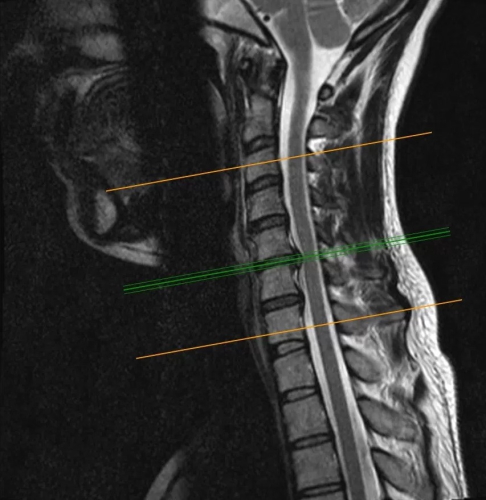

La radiculopatía cervical se produce más comúnmente secundario a una hernación de disco cervical, que puede conducir a la implantación de raíces nerviosas que salen del canal espinal. Los síntomas pueden ser cualquier combinación de dolor, adormecimiento, pérdida de reflejos y / o debilidad muscular. La mayoría de los pacientes generalmente responden al tratamiento conservador en forma de AINES, descanso y inyecciones epidurales de esteroides. Para los casos refractarios de un solo nivel, la disectomía cervical anterior y fusión (ACDF), laminotomía cervical posterior, o la artroplastia de disco cervical (CDA) son el principal del tratamiento.